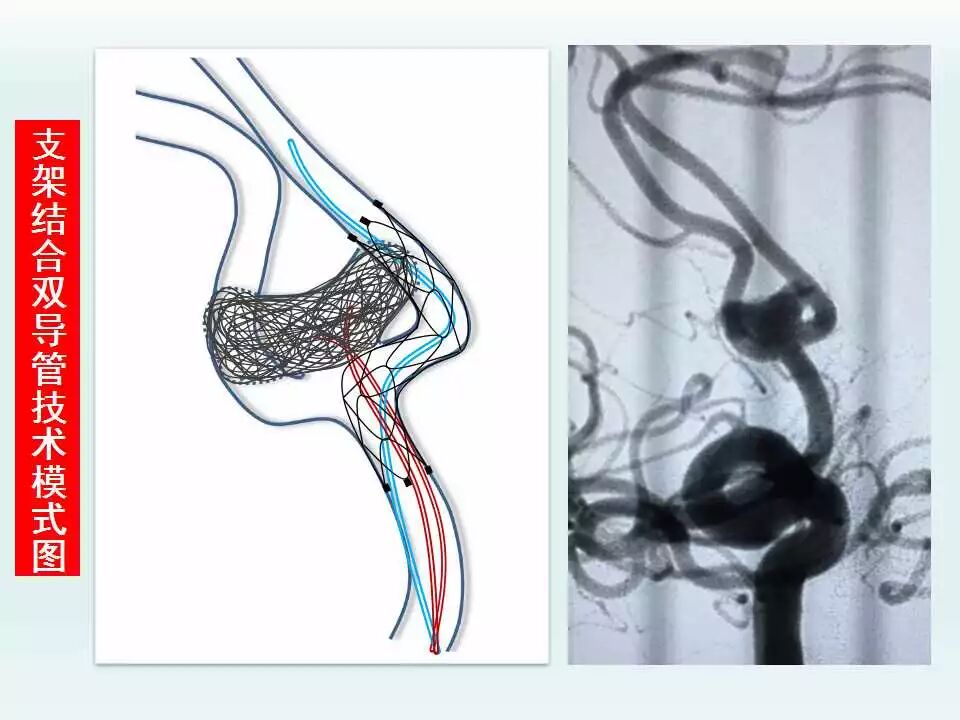

2003年开始神经介入工作,5年前在安徽省率先成立脑血管亚专业病区,每年的脑血管造影和血管内治疗颅内动脉瘤、脑动静脉畸形、颈内动脉海绵窦瘘及硬脑膜动静脉瘘等出血性疾病达1000台,并形成了急性期支架辅助弹簧圈治疗破裂宽颈动脉瘤、微小动脉瘤的血管内治疗和复杂动脉瘤的血管内治疗的特色,目前年血管内治疗颅内动脉瘤300例以上。